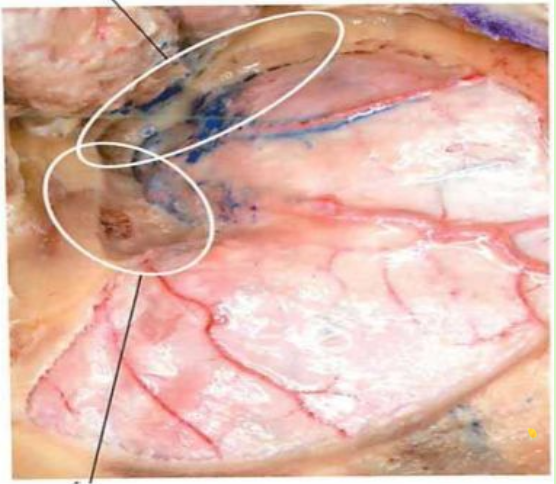

切开瘤膜,分块切除肿瘤

分离瘤膜边界,完整切除肿瘤

肿瘤残腔显示